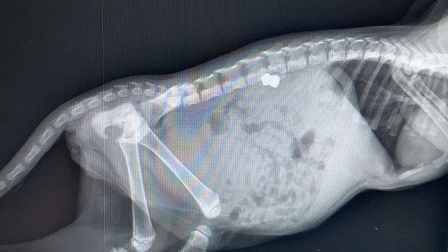

Presa a fucilate era rimasta intrappolata nella griglia anteriore di una Smart: l´intervento della polizia municipale di Castellammare del Golfo ha salvato la vita ad una gattina di pochi mesi impallinata con un fucile ad aria compressa.

La gattina è stata colpita alla schiena ed aveva difficoltà a muoversi: un uomo l´ha sentita miagolare dalla griglia anteriore di una macchina nel quartiere "case nuove" e lo ha segnalato alla polizia municipale. La gattina è stata poi curata dal veterinario Alessandro Gabellone, convenzionato con il Comune, che ha estratto dalla schiena della micina un piombino.

La gattina è stata colpita con un fucile ad aria compressa e dopo la rimozione del pallino e le cure, non è più in pericolo di vita: ora è in mani sicure perché già affidata alle attenzioni di alcuni volontari.